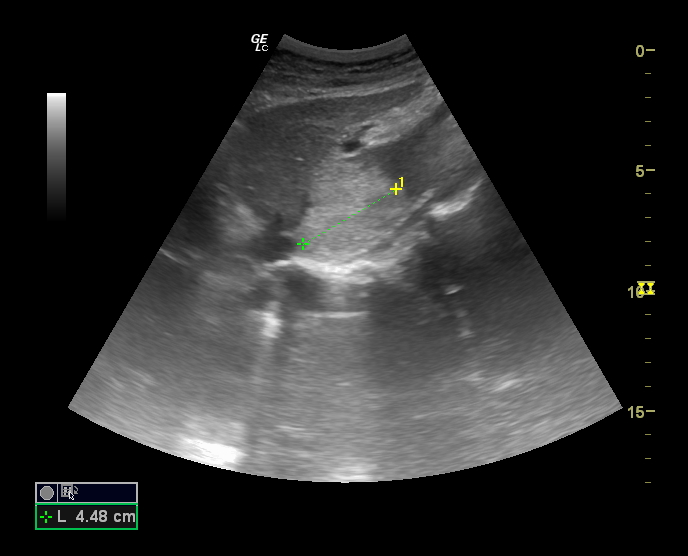

Hallazgos ecográficos

En la última ecografía realizada en febrero de 2023 presenta múltiples hemangiomas (lesiones hiperecogénicas), el de mayor tamaño en lóbulo caudado de 41 x 38 mm, segmento VIII dos, uno de 53 x 40 mm y otro de 17 mm, en segmento IV de 16 mm y en segmento VII de 9 mm.